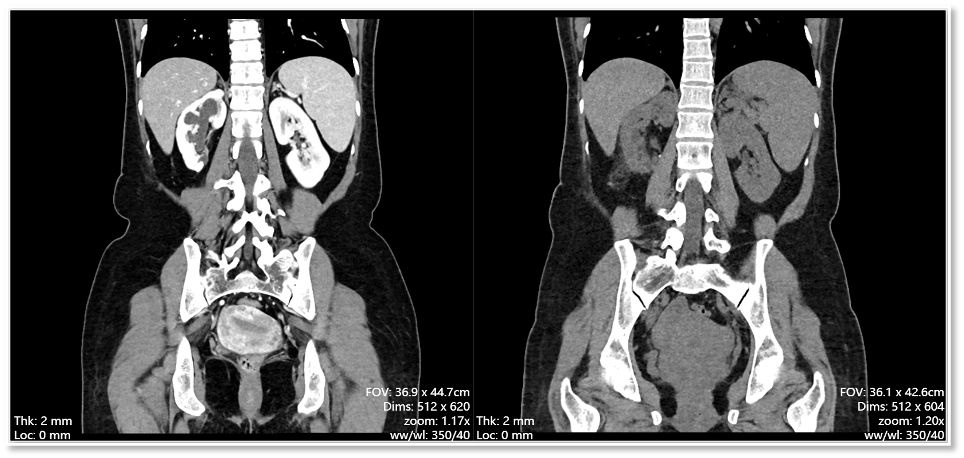

患者术前术后CT对照

术后,王女士恢复顺利,未出现任何并发症。三个月后的复查结果显示,积水基本消失,肾脏功能也得到了有效保留。